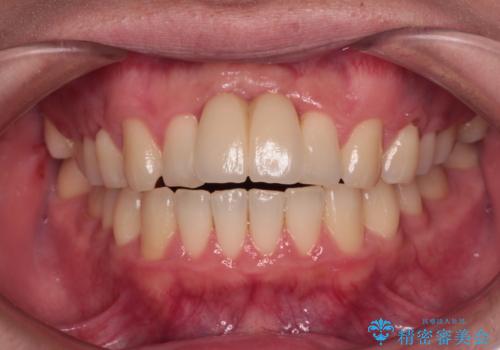

前歯のクロスバイト インビザラインによる矯正治療

インビザライン特有の、治療後半に奥歯が咬み合わないという事象が長引きました。

咬み合わないときの対処方法は色々とありますが、ゴムかけなどを活用して噛めるようにしました。